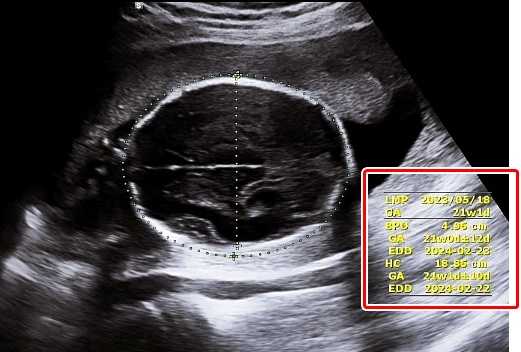

2. GA (Gestational Age): 임신기간, 임신주수

태아의 주수를 뜻하며 Ow Od (O week, O day), 주와 일수로 표기됩니다.

임신 몇 주 며칠인지 알 수 있어요.

3. EDD (Estimated Due Date): 분만 예정일

GA를 바탕으로 산정된 분만 예정일입니다.

EDC (Estimated Day of Confinement)라고도 하며 출산 예정일을 말합니다.

7. BPD (Biparietal Diameter): 머리직경

양쪽 옆통수 뼈와 뼈 사이의 길이를 말합니다.

8. HC (Head Circumference): 머리둘레

태아의 머리둘레입니다.